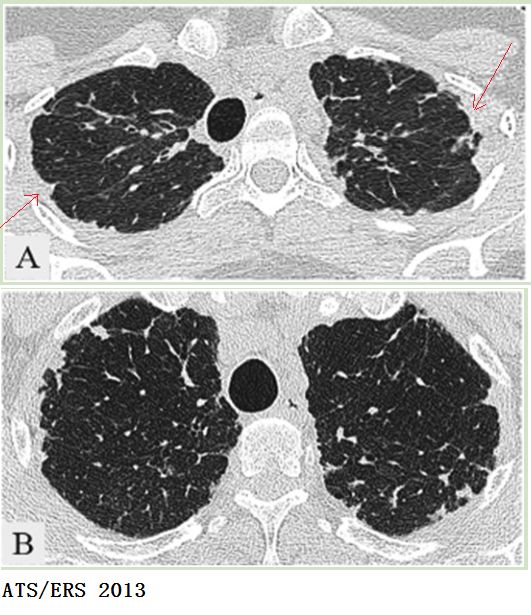

uip:普通型间质性肺炎ra:类风湿性关节炎下面看几例典型的蜂窝肺影像

特发性间质性肺炎的病理影像特点